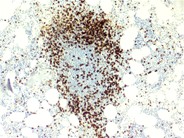

Bone marrow germinal center - 1.

Bone marrow biopsy was performed to stage a patient newly diagnosed with diffuse large B-cell lymphoma. The lymphoid nodule noted had the appearance of a germinal center with a blood vessel evident in the center.